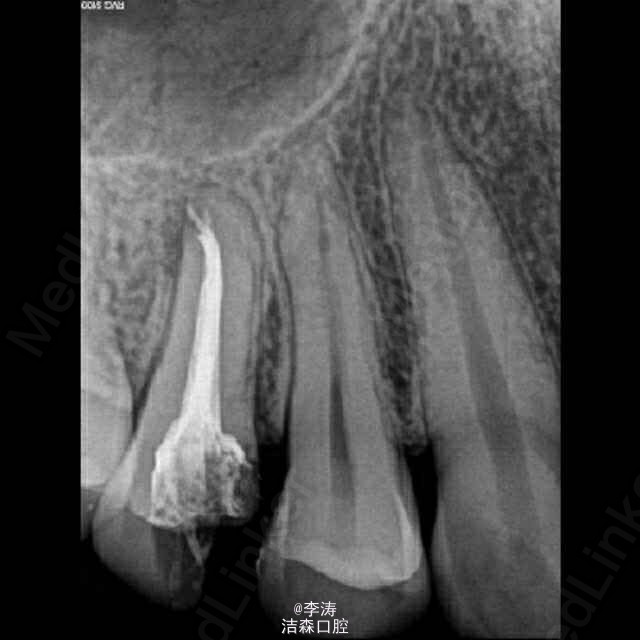

过台阶根管再治疗一例

15牙因根管治疗后牙折裂,行根管再治疗

年轻恒牙;根管再治疗;消除台阶